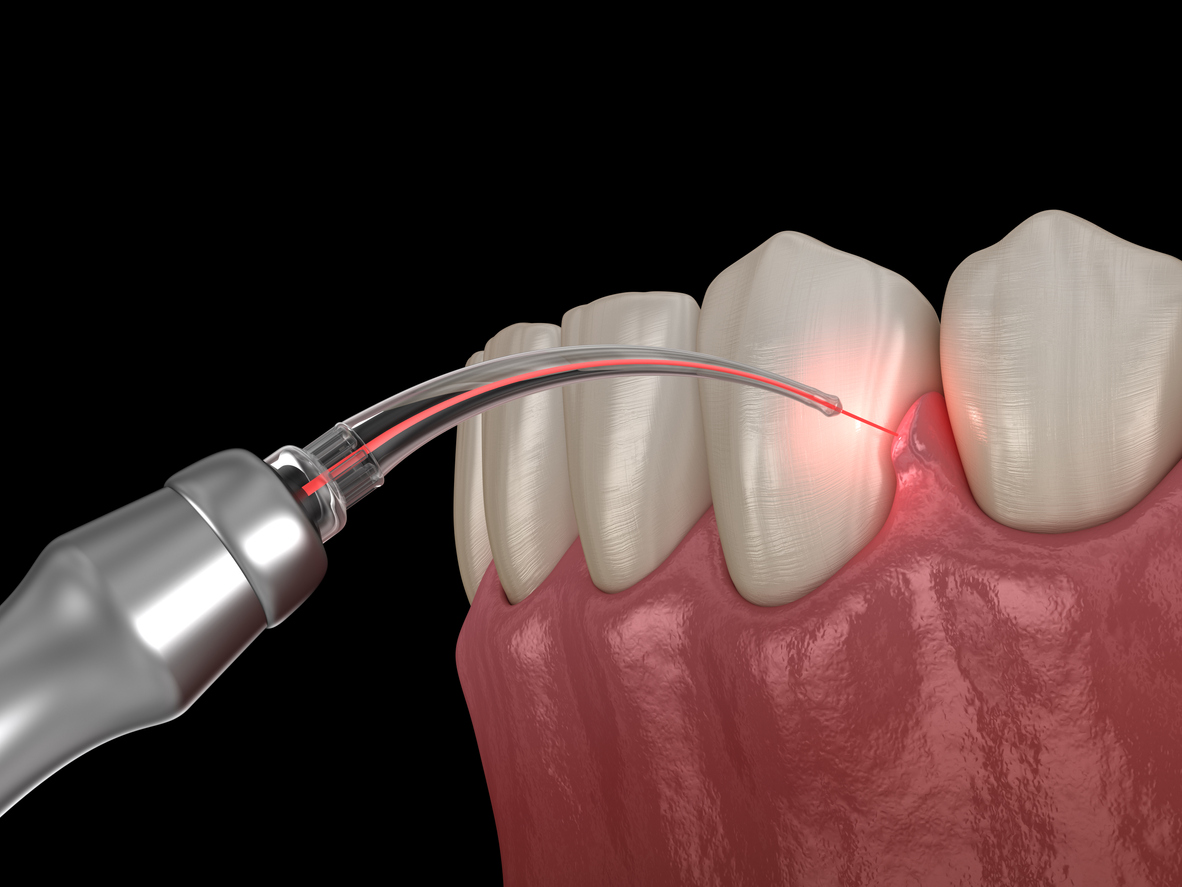

The material is placed into the bone void under visual inspection or under radiographic monitoring during open or percutaneous surgery.